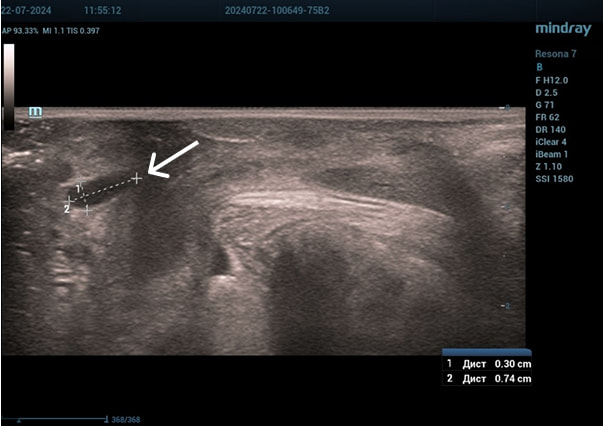

Эхограммы периуретральной области

Трансперинеальный доступ, линейный датчик.

Слева от уретры округлое образование с четкой капсулой и мелкодисперсной взвесью размерами 1,5×1,0 см (филлер с воспалением), справа — анэхогенное овоидное образование (филлер).

Эхограмма 1